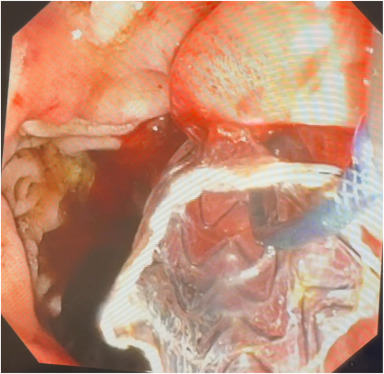

Matthew Eganhouse, MD, et al present a case of successful endoscopic therapy for bleeding in a walled-off necrosis cavity using through-the-scope clips, thermal therapy, and fibrin gel matrix. https://t.co/vmL7u5fP9K

#GITwitter